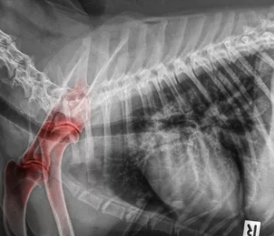

1. 슬개골탈구란?

슬개골탈구는 무릎 뼈(슬개골)가 정상 위치에서 벗어나 바깥쪽이나 안쪽으로 밀려나는 질환입니다.

특히 Grade 3~4의 경우 관절염, 근육 위축, 만성 통증으로 이어지기 쉬워 수술이 유일한 근본 치료입니다.